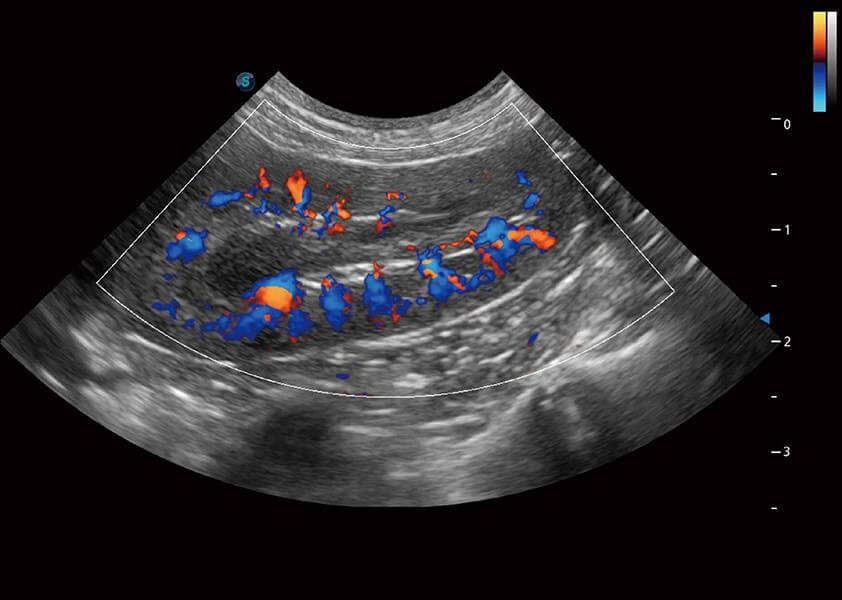

ProPet 60 作为一款高端台式动物超声设备,为动物医生的日常诊断提供了一系列贴合动物临床需求、解决临床实际问题的高级成像功能。凭借全系列高清探头,满足医生对腹部、心脏、生殖、浅表、肌骨等成像的所有需求,切实帮助您提升检查效率,提高诊断信心。